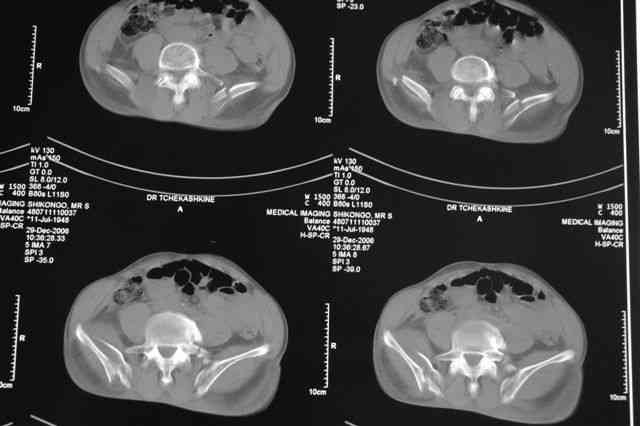

Я помню технику транссакральной фиксации тазового кольца длинными 5 мм Шанцами - повреждения типа В, в этом же случае задний отдел тоже вовлечен

т.е комбинированная нестабильность, поэтому вопрос - достаточно ли только двух Шанцев для стабилизации таза? Что вы думаете об anterior Right SI joint plating + tension band plating from the back.?

PS после фиксации бедра под Эопом посмотрел инлет и аутлет проекции, насколько репонируемо смещение правой половины таза *невооруженными*

Элегантная фиксация, поздравляю.Но ваш случай : одноплоскостная горизонтальная нестабильность Tyle B2.2 отличен от представленного мной - у

моего больного + вертикальная нестабильность за счет повреждения правого крестцово-подвздошного сочленения и перелома заднего отдела подвздошной

кости- С2 тип. Поэтому и возникла дилемма : выбор оптимальной фиксации заднего отдела:

По-поводу фиксации таза спонгиозными винтами. Данный способ все-таки показан для фиксации повреждения крестцово-подвздошного сочленения или переломов крестца. Мне кажется, что в данной случае ситуация иная - имеется перелом "основания" крыла подвздошной кости (в который вовлечена и поверхность, составляющая крестцово-подвздошное сочленение). Не уверен, что фиксация данного повреждения (и заднего полукольца) винтами будет стабильной, так как именно на уровне 1-2 крестцовых позвонков (где обычно вводят винты) линия перелома уходит в латеральном направлении от крестцово-подвздошного сочленения.

PI>По-поводу фиксации таза спонгиозными винтами. Данный способ все-таки показан

для фиксации повреждения крестцово-подвздошного сочленения или переломов крестца. Мне кажется, что в данной случае ситуация иная - имеется перелом

"основания" крыла подвздошной кости (в который вовлечена и поверхность, составляющая крестцово-подвздошное сочленение). Не уверен, что фиксация данного повреждения (и заднего полукольца) винтами будет стабильной, так как

именно на уровне 1-2 крестцовых позвонков (где обычно вводят винты) линия перелома уходит в

латеральном направлении от крестцово-подвздошного сочленения.

Я просмотрел томограммы и у меня создалось впечатление, что винтам есть за что *зацепиться*. В сочетании с 5 мм Шанц винтами, проведенными через нижне-переднюю ость спереди назад через КП сочленения -стабильность тазового кольца должна восстановиться. - Это , конечно, при условии , что закрытая рнепозиция будет успешной.